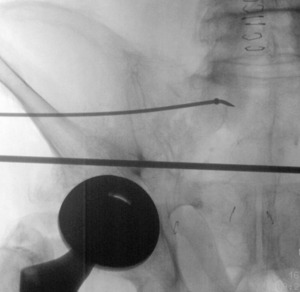

A 1.6 mm Kirschner wire (K-wire) is placed in the posterior superior quadrant down to bone. Start point is confirmed using inlet and outlet views. Once a satisfactory start point is located, the wire is tapped into the bone with a mallet. A skin incision is made, then the scalpel is run along the pin to incise fascia. A drill sleeve is placed over the pin through the incision onto bone. The K-wire is exchanged for a 2.8mm guide pin which is inserted at least 3cm into the lateral ilium, aimed toward the S1 body (Figure 1). The 3cm is necessary to match the proximal straight portion of the flexible implant. When approaching the neural foramen, a lateral image may be taken to ensure the pin is caudal to the ilio-cortical density and cephalad to the S1 tunnel to avoid injury to the L5 or S1 nerve roots.